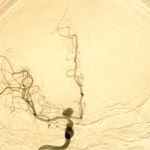

- Aneurismas cerebrais

- Malformações arteriovenosas cerebrais

- Clipagem de aneurisma cerebral